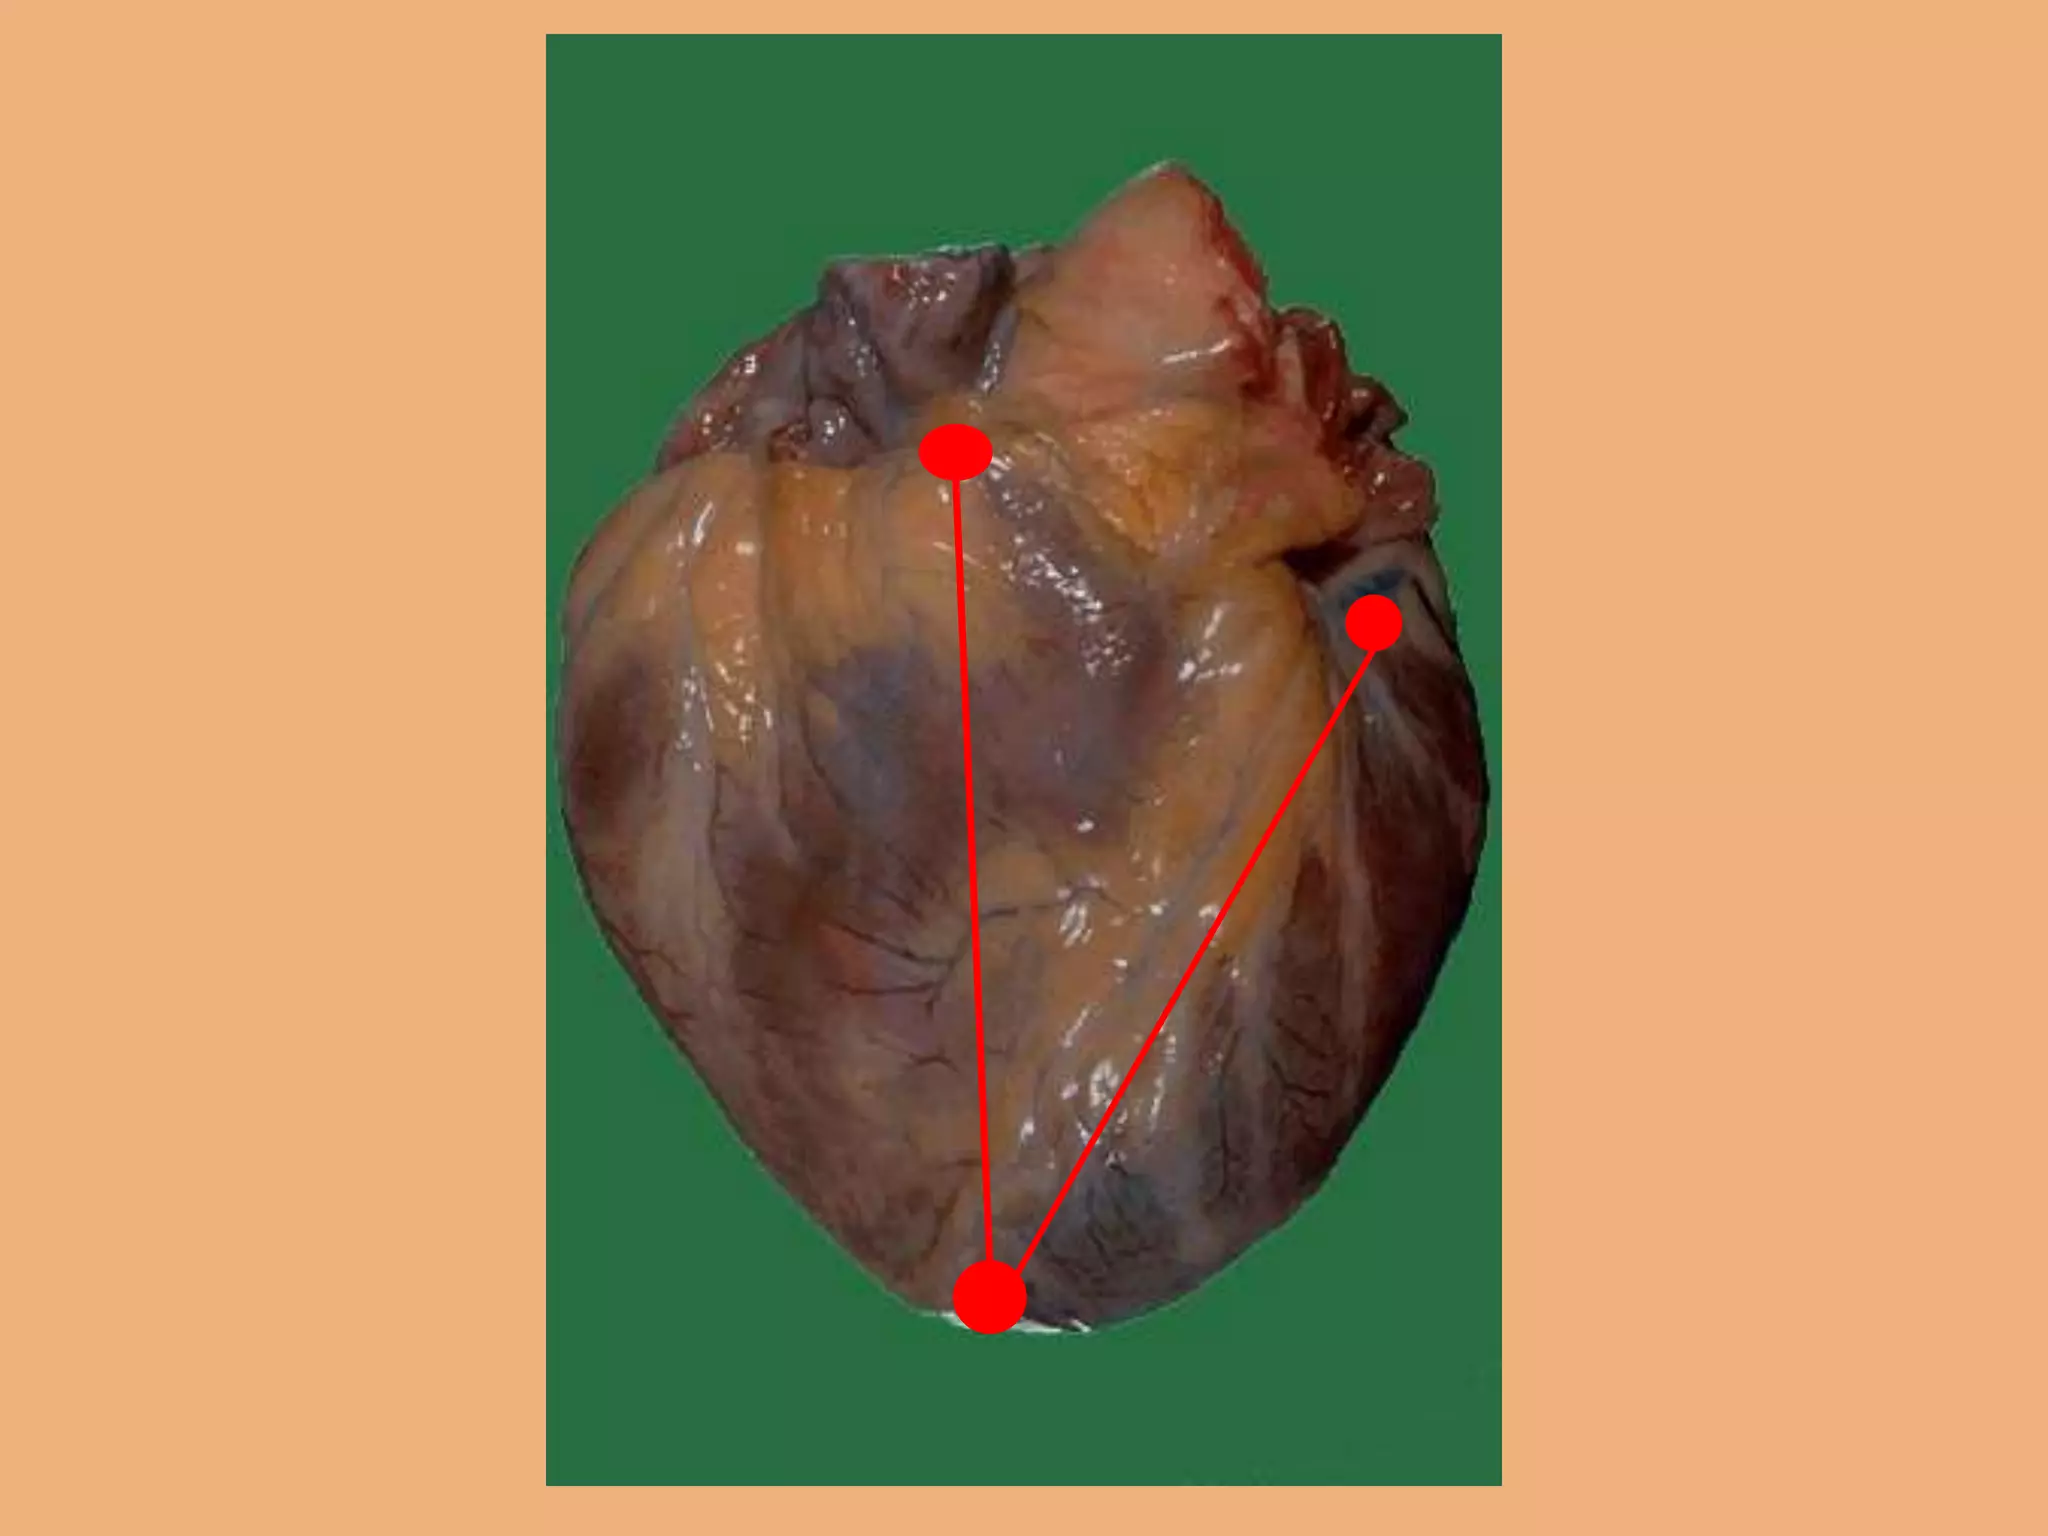

Cardiac dissection methods:

1. Inflow-outflow method

2. Short-axis method

3. Four chamber method

4. Long axis method

5.Base of heart method

6.Window method

7.Unrolling method

8.Partition method.

Cardiac dissection methods: 1.Inflow-outflow method 2. Short-axis method 3. Four chamber method 4. Long axis method 5.Base of heart method 6.Window method 7.Unrolling method 8.Partition method. Useful for demonstrating cardiac pathology Anatomic teaching and museum specimen demonstration s/ preparations. Considerab le Mutilation of the heart